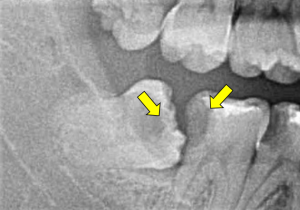

むし歯の元となるバイ菌が増えると、親知らずはむし歯になります。親知らずだけのむし歯であれば、親知らずを抜歯してしまえば全て解決します。しかし、親知らずと近接している歯までむし歯になることがしばしばあります。親知らずの手前の歯は一生必要な歯ですが、むし歯の位置によってははとても治療がしにくく、歯を失うきっかけとなってしまうこともあるのです。